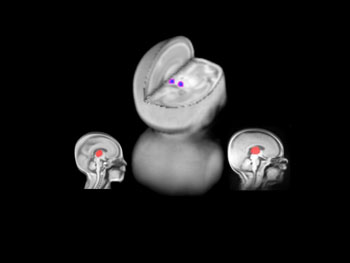

Using magnetic resonance imaging to study brain growth in very preterm babies we found that a specialized region of the brain (red), the thalamus (involved in relaying pain and touch information to the brain) showed a decrease in size (blue-purple) in those babies exposed to more painful procedures. Further, babies born at less than 28 weeks of gestation had the most pronounced changes in the thalamus.

MRI cross section of brain. Two shown in profile, one as a 3D image.